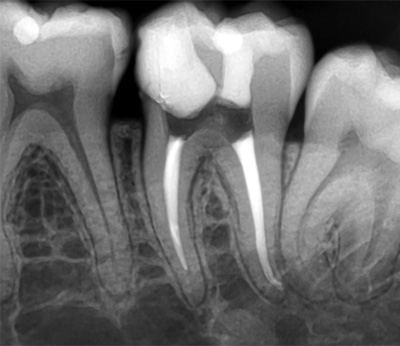

Radiografia intraorala reprezinta examenul radiologic care ofera cea mai fidela imagine, la scara 1:1, pentru examinarea detaliilor de structura dentoalveolara si a proceselor patologice ce se pot gasi la acest nivel. Pe o radiografie retroalveolara, cu o singura expunere, pot fi vizualizati intre 1-3 dinti alaturati. Pentru dintii pluriradiculari pot fi necesare mai multe expuneri, pentru vizualizarea radacinilor din diferite unghiuri (incidente excentrice).